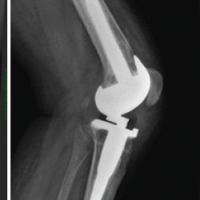

A 38-year-old male with a history of right shoulder instability in the past was managed with the Latarjet procedure 4 years ago. The patient had an uneventful post-surgical period, but symptoms recurred a year later without any significant event. He presented to us with complaints of right shoulder pain and instability since 3 years, having experienced multiple episodes of dislocations, which were managed with closed reduction at different centers. On examination, the Beighton score was five. 1 cm wasting was noted in the right arm. Sensations over the arm were intact. Tests for anterior instability, such as apprehension, relocation-release, and anterior drawer, were positive. There were no signs of instability in posterior and inferior directions. He had a nearly complete range of motion in all planes but was apprehensive to use the arm for overhead activities and lifting heavy objects. X-ray and computed tomography (CT) scan were done, which revealed a displaced as well as a broken screw near the right glenoid, likely from the previous surgery (Fig. 1 and 2). The anteroinferior part of the glenoid appeared to be resorbed. Bone loss was quantified using the perfect circle method in oblique sagittal plane, which was approximately 27% (Fig. 3). Infective etiology was ruled out via clinical examination and radiological investigations.

Figure 1: X-ray on presentation. (a) Anteroposterior X-ray in 10° abduction, (b) Anteroposterior X-ray in 60° abduction, both showing a displaced screw in soft-tissue marked with a black arrow.